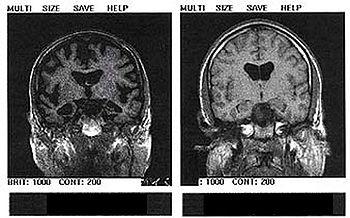

كمايطلب الأطباء صور الأشعة المقطعية وصور الرنين المغناطيسي للمخ brain MRIs or CT scans والتي تظهر ضمور المخ في هذه الحالات[4]

350px_Alzheimer__s_disease___MRI__dumb_version_.jpg

رسم بالأشعة لدماغ سليم (على اليمين) و آخر مصاب(على اليسار)

* ويُكتشف المرض بوجود رقع ، وكتل حول وداخل خلايا المخ. وتتكون الرقع من نوع من البروتين(بيتا أماي لويد) الموجود بالمخ ، بينما تتكون الكتل داخل الخلايا العصبية بفعل تشوه يصيب بروتينا آخر. وبموت الخلايا العصبية ، يتقلص المخ ، ويفقد مظهره المتجعد.